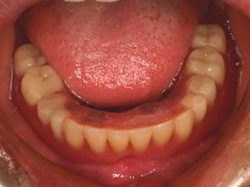

両側5歯症例両側5歯症例両側5歯症例 主訴-義歯のバネが壊れて手前の歯が痛んできた。 術前(旧義歯装着、鏡像) 術前(下顎粘膜面、鏡像)術前(下顎粘膜面、鏡像)術前(下顎粘膜面、鏡像) 術前レントゲン術前レントゲン術前レントゲン 術前口腔内(正面観)術前口腔内(正面観)術前口腔内(正面観)

術後(鏡像)術後(鏡像)術後(鏡像) 術後口腔内(正面観)術後口腔内(正面観)術後口腔内(正面観)もう入れ歯は要らなくなりました。 術後レントゲン術後レントゲン術後レントゲン